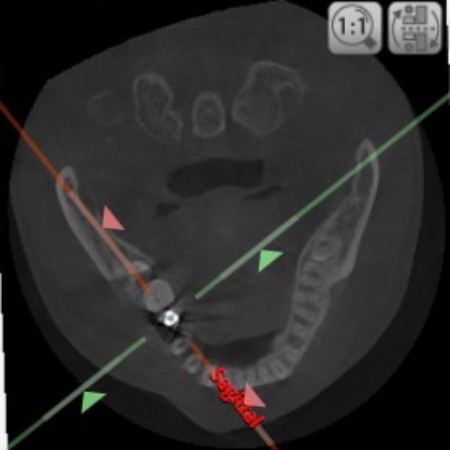

2ヶ月後に傷口がしっかりとふさがったことを確認できたため、CTを撮影してインプラントの治療計画を立て、後日インプラントを埋め込む手術を行いました。

手術の際、インプラントを埋め込む骨の中に抜歯後の傷が修復される過程でできた肉芽組織が見られたため、手術時に専用の器具を用いて取り除いてからインプラントを埋め込み、縫合しました。

治療中